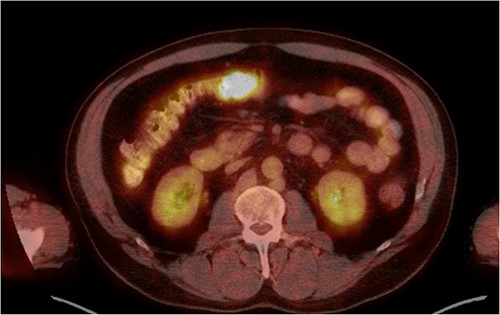

He was then referred to gastroenterology and underwent diagnostic colonoscopy that showed a large polypoid mass in the transverse colon that was partially obstructing. Gastroenterology then obtained a CT scan of the chest, abdomen and pelvis that showed wall thickening of the colon (Figs 1–3). Ultimately when pathology confirmed malignant melanoma, a PET scan was ordered that showed increased uptake at the previously seen and biopsied transverse colon mass (Fig. 4).